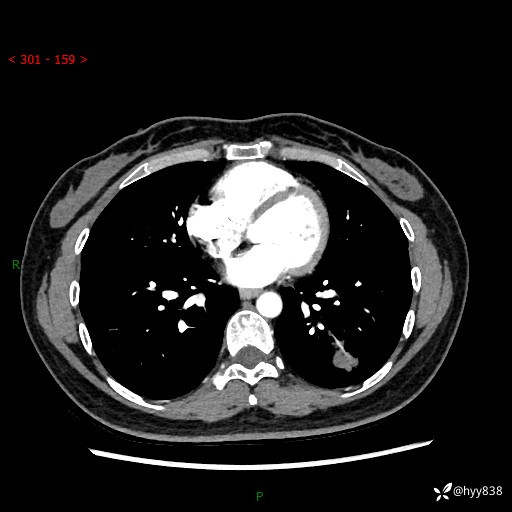

【患者信息】:36岁/女

【主诉】:左侧下胸部阵发性疼痛2周,乏力1周

【现病史及既往史】:患者自诉2周前饮酒后出现左侧下胸部阵发性疼痛,不随呼吸改变,无咳嗽咳痰、头晕头痛、咳血、呼吸困难等不适,于当地第一人民医院查胸部CT提示肺部感染,随后前往我院门诊给予抗感染(左氧氟沙星)治疗1周,自诉胸痛较前好转,感乏力、头晕,偶尔干咳,无咳痰,无发热、畏寒、胸闷、咯血、四肢酸痛、腹泻、腹痛等不适,门诊复查胸部CT提示:左肺下叶感染,病灶较前增加增大,遂以“肺部感染”收入我科。 起病以来,患者精神、饮食、睡眠可,大小便正常,体力体重无明显变化。

【检查】:胸部CT增强(外院平扫)